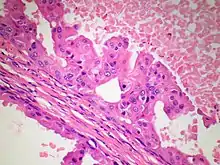

Non-invasive apocrine carcinoma of the breast, i.e. apocrine carcinoma in situ, is classified as a variant of the ductal carcinoma in situ tumors of the breast; it is therefore termed apocrine ductal carcinoma in situ (ADCIS).[9] ADCIS tumors have appreciable areas with apocrine tissue-like histopathology, i.e. areas composed of apocrine cells that have, to varying extents, the abnormal cytoplasmic, nuclear, and nucleolar features found in PACB (see Fig 4). Unlike PACB, the apocrine carcinoma cells in ADCIS have by definition not spread beyond their ducts of origin to invade nearby non-ductal tissue and have not metastasized to local lymph nodes or distant tissues.[4] While there is no consensus on the criteria used for its diagnosis, ADCIS is most often defined as a non-invasive breast tumor consisting of lactiferous ducts that are filled with neoplastic apocrine cells;[4] the cells in these tumors, similar to those in PACB, are estrogen receptor-negative, progesterone-receptor negative, and, in at least 10% of these cells, androgen receptor-positive.[9] Some studies have classified ADCIS as low, intermediate, or high nuclear grade based on how closely the nuclei of their tumor's apocrine cells resemble the nuclei of normal breast cells. In general, high nuclear grade tumor cells have more abnormal nuclei and indicate that this tumor is more aggressive than a lower grade tumor. Low- and intermediate-grade ADCIS tumors may be misdiagnosed as non-cancerous lesions (e.g. as atypical apocrine metaplasia or atypical apocrine hyperplasia) because of their more benign microscopic appearance.[4] ADCIS tumors often have architectural patterns consisting of cribriform (riddled with small holes), micropapillary (thin finger-like growths) and/or solid growth (i.e. do not contain cysts or liquid areas),[4] sites with necrosis, and/or sites with microcalcifications; while these microscopic findings are more common in high nuclear grade ADCIS, their presence supports the diagnosis of ADCIS in low and intermediate tumors.[9] Some authors have proposed that in situ ductal tumors with apocrine histopathology should be larger than 0.2 centimeters in order to be diagnosed as ADCIS.[4][9]